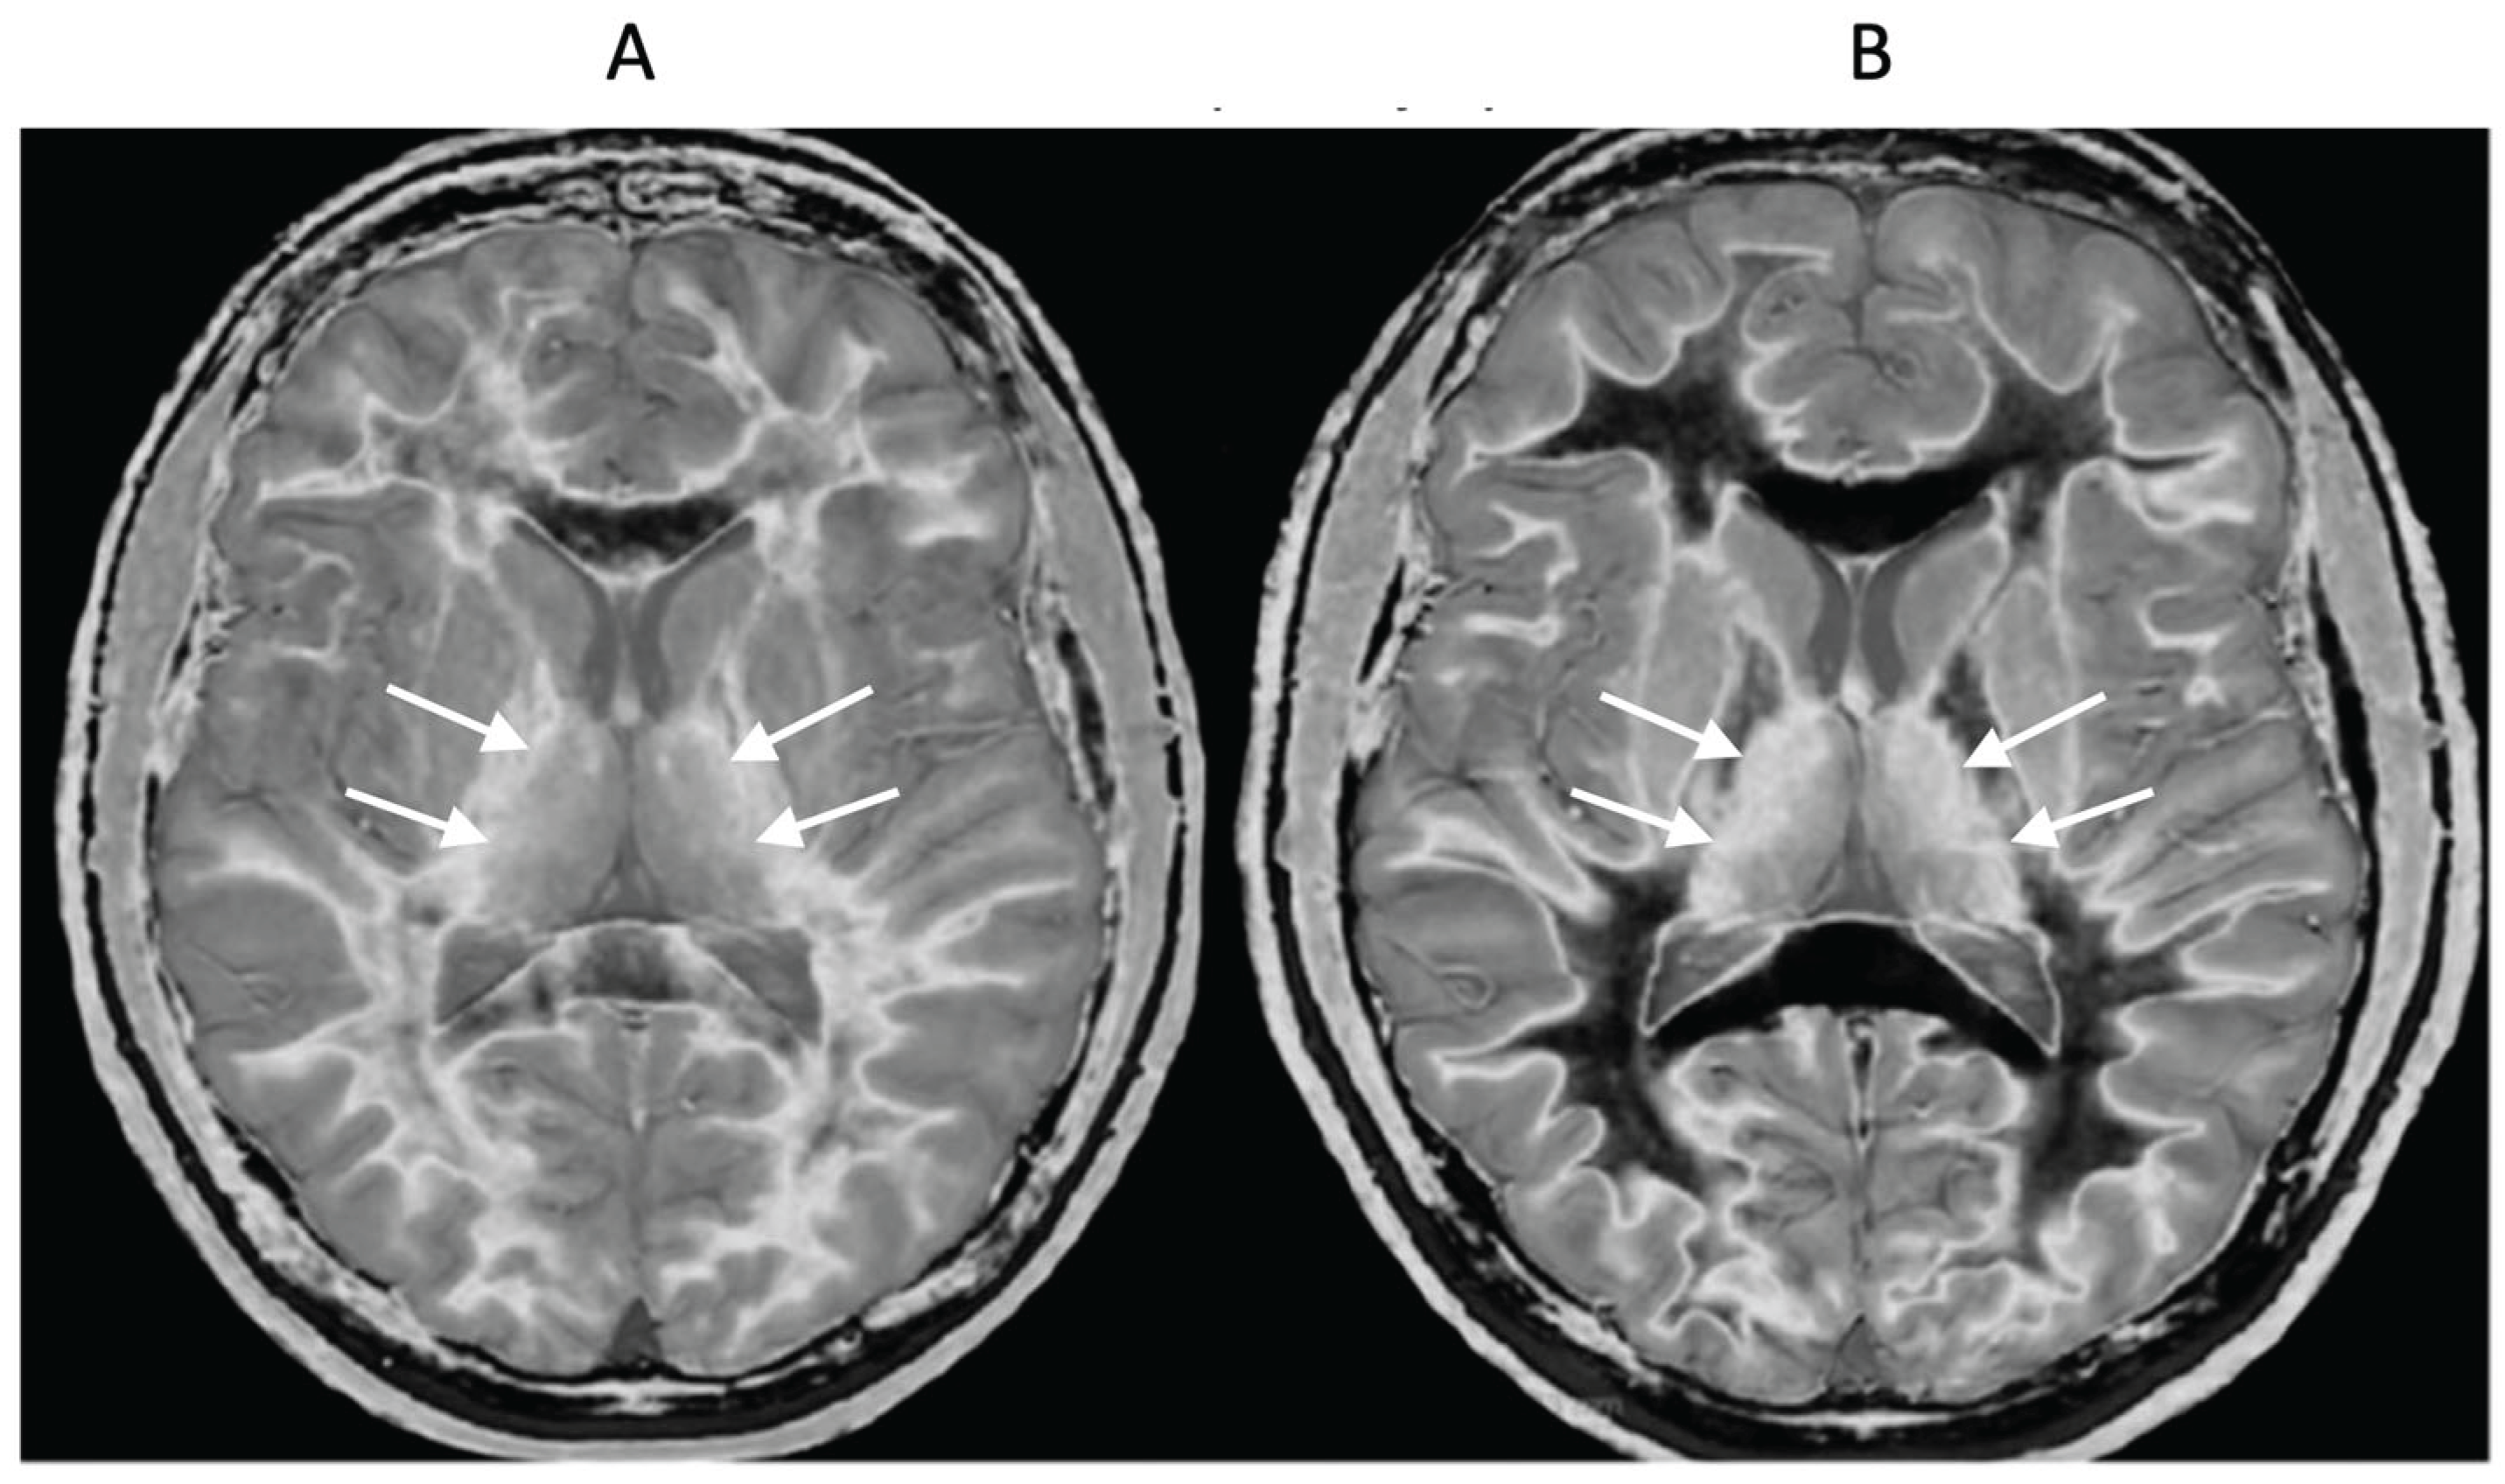

- Multiple Sclerosis (MS)